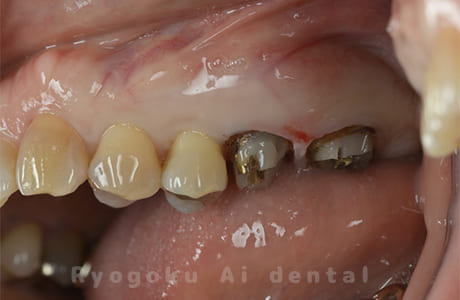

Case02

-

- 原因

- 重度縁下カリエス、慢性根尖性歯周炎

- 治療期間

- 約3ヶ月(最終補綴装着まで含む)

- 治療内容

- クラウンレングスニング+歯周外科+マイクロエンド

- 治療費用

- 165,000円(最終補綴を除く)

他院で抜歯を宣告された患者様です。歯の根の治療(マイクロエンド)と歯周外科・クラウンレングスニングを行いました。

<リスク・副作用>

手術後は痛み、腫れ、痺れ、青あざなどの副作用が生じます。痛みは痛み止めを処方しますが、腫れ、青あざは1週間程度生じる場合があります。また、部位によっては神経の走行が複雑で、痺れが残り、長期的にお薬を処方する場合があります。